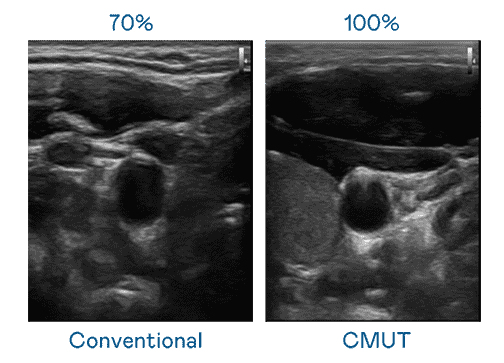

CMUT 技术是一种用电容式微机电元件来产生超音波讯号的技术。。与传统 PZT 压电式技术相比,,,CMUT 频宽增加 30%,,更宽频的超音波讯号让影像解析度大幅提升,,,是实现高影像品质医疗超音波扫描、、促进精准医疗发展的关键技术。。

大频宽带来超清晰影像

超音波影像的解析度高低,,,首先取决于探头能发出的讯号频宽。。。。YAXIN111 CMUT 可提供高清晰的超音波讯号,,,提供高频宽、、、、高灵敏度、、影像纹理细节更高的超音波影像,,,协助医护人员缩短影像判读时间及利用精准的医疗影像进行诊断。。。。